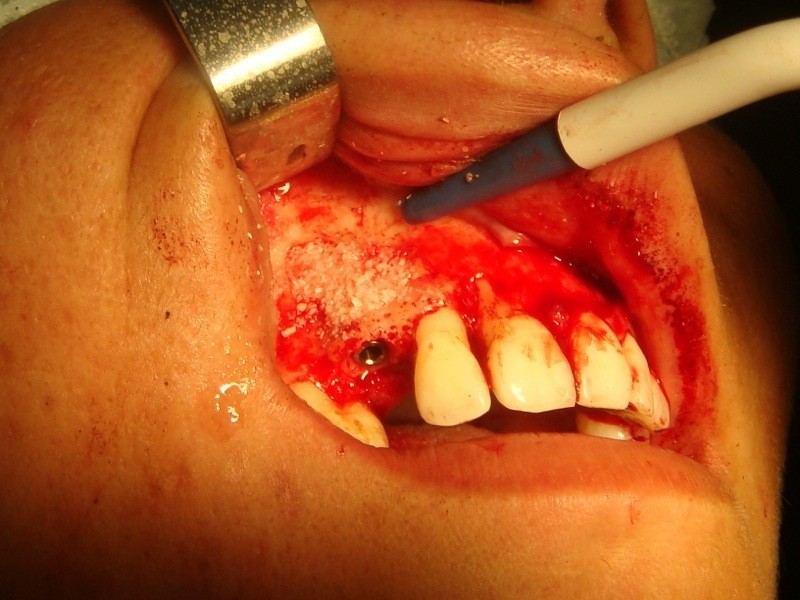

Implantologia avanzata con contestuale rimozione impianti e cisti

Video di una Parte dell'intervento in cui si puo' vedere la comunicazione tra impianti rimossi e pavimento nasale.